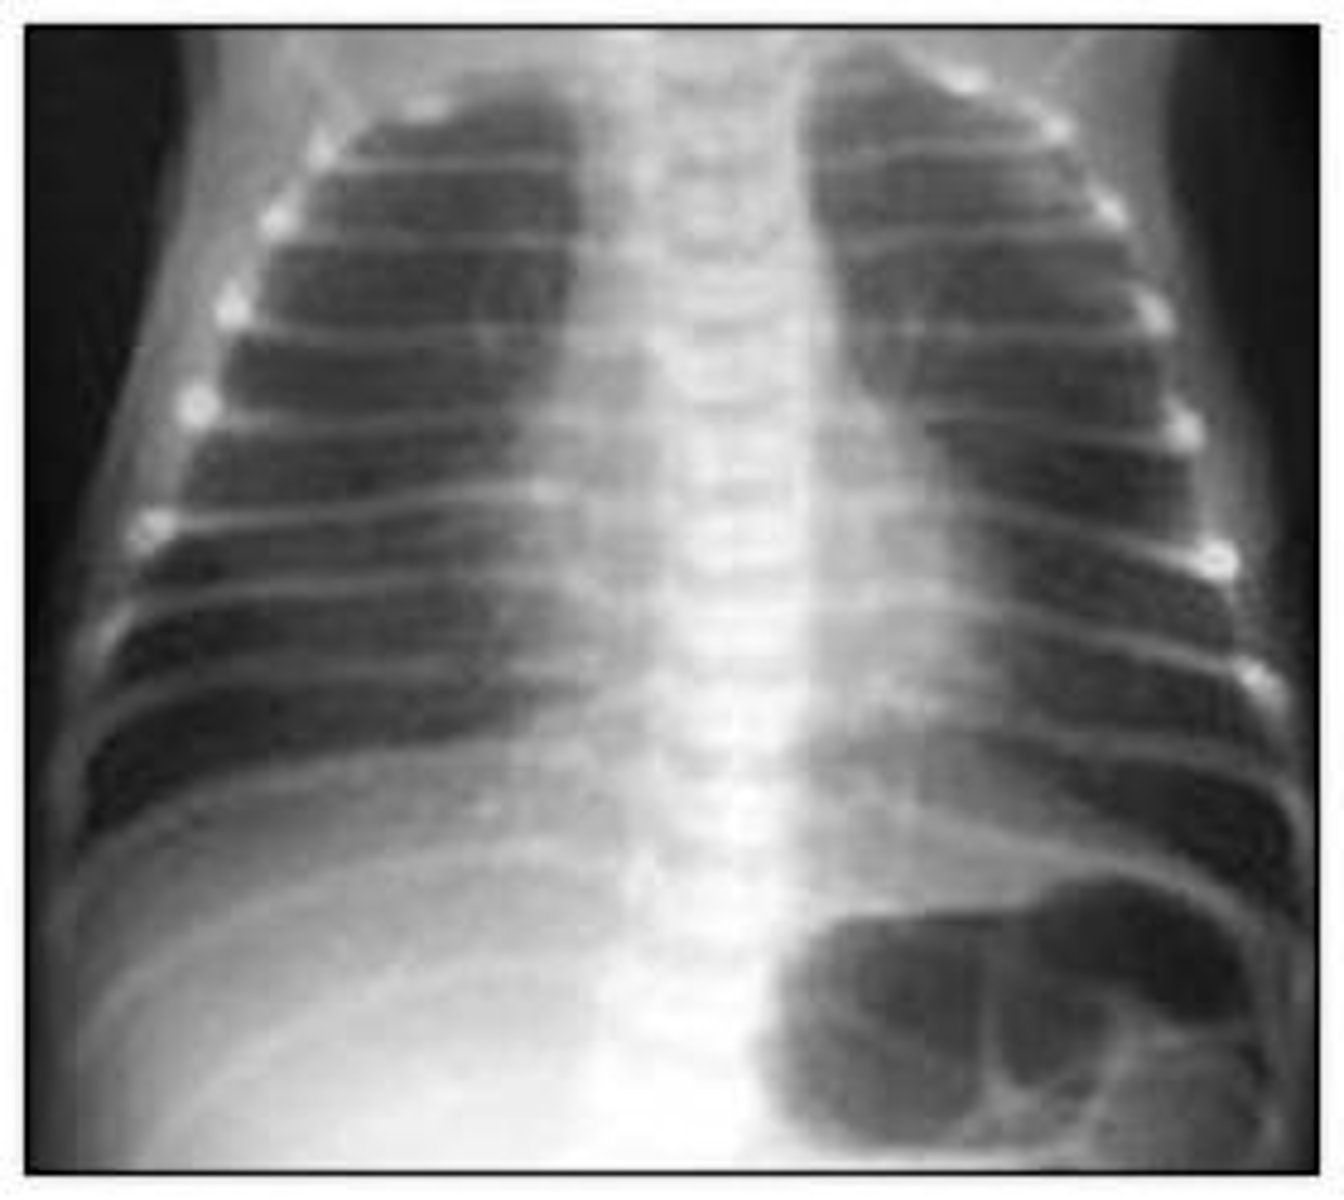

RDS

Prenatal Dx: L/S<2, give antenatal betamethasone

Pathophys: Surfactant def, can't keep alveoli open.

Txt: O2 therapy with nasal CPAP to keep alveoli open

32 wk premie has dyspnea, RR of 80 w/ nasal flaring.

- Prenatal Dx?

- Pathophys?

- Txt?